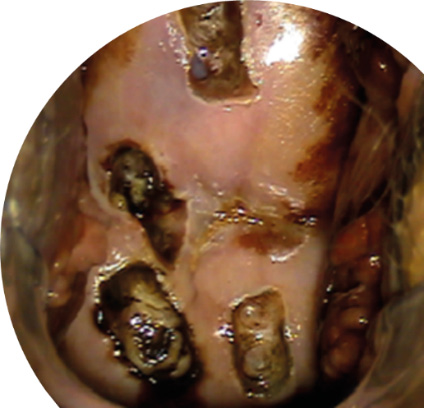

The first patient in group 1 underwent cervical biopsy during pregnancy due to suspected invasion (cytologically confirmed high-grade squamous intraepithelial lesion (HSIL), the presence of coarse acetowhite epithelium, and mosaicism and punctation on extended colposcopy). The biopsy was conducted between 16 and 17 weeks of gestation, resulting in the initial diagnosis. After insertion of a vaginal speculum (a condom was placed on the speculum so that the vaginal walls would not interfere with the procedure), the cervix and vagina were irrigated with a saline solution and cavitated with low-frequency ultrasound. An extended colposcopy was then performed to locate the biopsy site. The biopsy was performed in the absence of anesthesia using a small loop on the Fotek device in a single pass in the cutting mode with a power of 60 W (Fig. 1).

Fig. 1. Cervical biopsy in a pregnant patient under videocolposcopic guidance (author’s photo).

Subsequently, additional hemostasis was achieved through the application of an electrode and a power of 60 W, operating in the soft mode on the Fotek device. The hemostasis was further augmented by the use of an argon plasma torch on the same device. The obtained specimen of cervical tissue was subsequently sent for histopathology. A tampon soaked in antiseptic was inserted into the vagina for several hours.